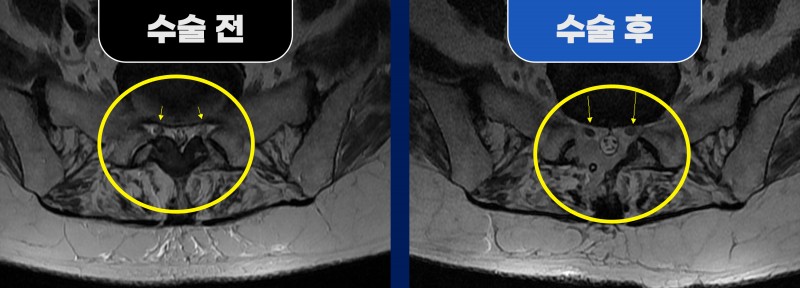

■ Before (수술 전)

MRI 검사 결과, 요추 5번(L5)/천추 1번(S1) 구간의 황색인대가 과도하게 두꺼워진 협착증 소견이 확인되었습니다.

■ After (수술 후)

환자분은 양방향 내시경 수술을 받으셨습니다.

수술 중 석회화된 황색인대가 신경을 심하게 압박해 신경이 붓고 충혈된 모습이 확인되었고,

이를 제거하여 신경 공간을 확보했습니다.